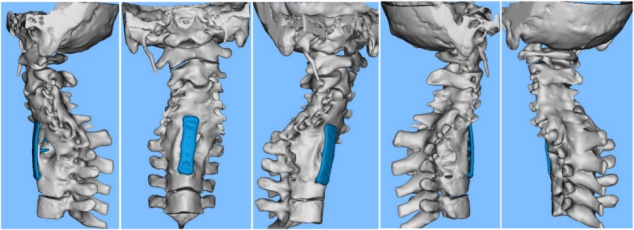

Using digital medical technology plans to simulate the surgery

Considering the complexity and severity of the patient's conditions based on comprehensive evaluations, Prof. Liao Bo's team successfully implemented an "anterior and posterior scoliosis-correction of cervicothoracic spinal deformity, spinal hernia release, and dural hernia repair" in full cooperation with a multi-disciplinary team.